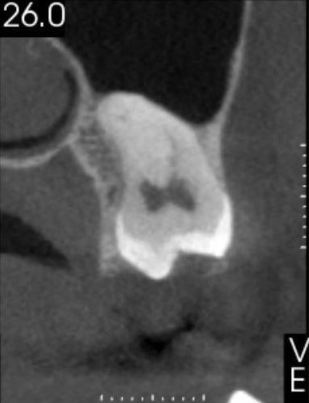

Veja alguns casos de sucesso